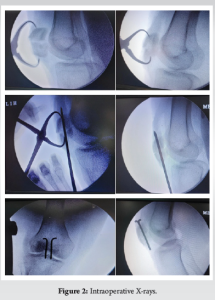

The patella serves as a pivotal component in the biomechanical function of the knee extensor apparatus [1]. Fractures of the patella have the potential to disrupt this mechanism, particularly when combined with incongruent posterior articular surfaces, leading to persistent issues like discomfort arising from femoropatellar arthritis [2,3]. Patellar fractures commonly stem from two primary mechanisms: Direct impact on the anterior knee or indirect injury resulting from eccentric contraction of the quadriceps muscle [4]. Surgical intervention becomes necessary in about one-third of patients affected by these fractures. Tension band wiring using stainless-steel wires has long been considered the gold standard for surgically managing displaced patellar fractures (Fig. 1 and 2) This technique effectively converts tension from muscle pull into compression at the fracture’s articular side, promoting improved fracture union by providing absolute stability through interfragmentary compression in bending fractures. However, its widespread use has been subject to debate due to the high incidence of resurgery rates attributed to issues such as implant impingement, skin infection, and wire breakage [5,6] (Fig. 3 and 4). Also for multifragmented stellate fracture, where encircle is required, SS wires require multiple passes through retinaculum with 4-mm-thick wire passer which is more traumatic. An alternative to traditional metal wire for patellar fracture fixation is non-absorbable suture, such as fiber tape (Fig. 5), which has been shown to yield similar outcomes with a reduced complication rate and comparable strength in biomechanical studies. Multiple passes in encirclage method for comminuted fractures with fiber tape is less traumatic with 2-mm needle. Research conducted by Arthrex found that fibreTape exhibited significant strength at 3 mm elongation and shows good loop integrity [7].

The procedural steps closely resemble those of the classic tension band wiring technique, with no specialized instruments required beyond the standard orthopedic trauma instruments set and a fiber tape alongside two 2.0-mm Kirshner wires. Carefully anatomically reduce the transverse fracture and secure it using a pointed reduction forceps, ensuring confirmation of reduction through fluoroscopy.

- Insert two parallel Kirschner wires across and proximal and distal fragments (Fig. 6).

- Thread the fiber tape in a figure of 8 manner across quadriceps tendon or patellar tendon and below the two K wires.

- After crossing over the anterior surface of patella in figure of 8 manner, Fiber tape is tied tightly with multiple reverse half hitches at superolateral region of patella, until the desired compression is achieved at the fracture site. This is followed by burying the knot under retinaculum. The torn retinaculum is repaired with absorbable suture.

- Trim the ends of the K-wires.

- Bend the ends of the K wires posteriorly.

- Conclude the procedure by suturing the retinaculum.

In comminuted fractures where encirclage is preferred, the fiber tape is initially threaded beneath the patellar tendon before being wrapped circumferentially around the patella bone. Utilizing a tensioner, the fiber tape is then tensioned to a force of 70–90 pound force (Fig. 6). Subsequently, the reduction is assessed intraoperatively, knots are securely buried under the retinaculum, and excess is trimmed after checking the stability of the reduction by performing flexion and extension movements of the knee (Fig. 7).

Operative intervention is necessary for every unstable patellar fracture. Tension band wiring, aligning with AO principles, stands as the most widely accepted technique for treating displaced patellar fractures. However, various other methods combining fixation techniques such as K-wires, screws, and cerclage wiring have been documented. Internal fixation is crucial for maintaining fracture reduction until complete healing is achieved, while conventional stainless-steel wires can offer stability, their use often leads to symptomatic hardware and other complications [8]. Consequently, alternative materials with superior tensile strength, as demonstrated in biomechanical studies, have been investigated. Fiber tape, a braided tape shaped polyblend suture, exhibits a tensile strength exceeding 540N, surpassing the 494 N strength of 18 gauge steel wires. Furthermore, testing with cadaveric tendons revealed a pull through force of approximately 189 N for fiber tape, Notably displacement of hardware with stainless-steel wires, resulting in hardware prominence [9,10]. Utilizing fiber tape eliminates the need for implant removal due to skin impingement, addressing a common issue associated with metallic wires. Furthermore, fiber tape exhibits resilience without fatigue, lesser tissue damage, minimizing the risk of implant failure often observed with metal wire breakage and if encirclage is the treatment of choice then it is MRI compatible also [10,11]. Moreover, unlike fixation with metallic wires, fiber tape can be employed not only for simple or comminuted patellar fractures but also as an effective fixation method for distal pole avulsion fractures (Fig. 10-12). However, it is worth noting that the tightness of the fixation knot is surgeon dependent, posing a potential drawback. This issue can be addressed by implementing multiple sequential tightening of 3–4 reverse half hitches on alternating post knots to ensure optimal fixation [12,13]. In our study, we observed a notable decrease in the number of patients requiring re operation, resulting in reduced strain on resources and financial benefits for the patients.